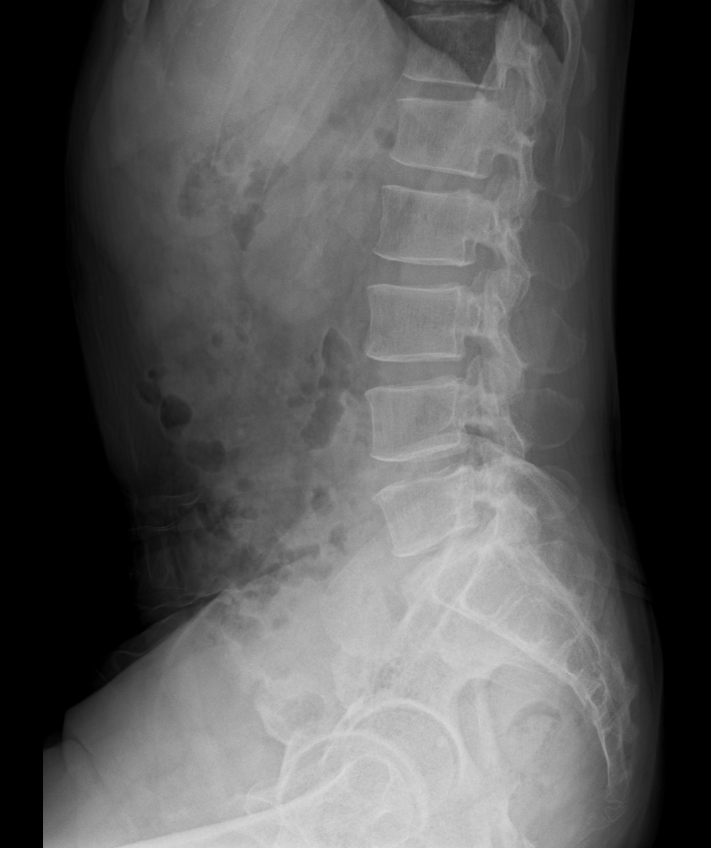

X-ray, 너무 자주 찍는 것은 지양해야 합니다

병원 진료 중 “혹시 모르니까 X-ray 한 번 찍어볼까요?”라는 말을 쉽게 듣게 됩니다.특히 팔·다리를 살짝 부딪치거나 교통사고 후 목이 뻣뻣할 때, 혹은 아이가 놀이터에서 넘어졌을 때 등 많은 분들이 X-ray 촬영을 요구합니다. 하지만 모든 통증이 X-ray를 필요로 하는 것은 아닙니다. X-ray는 뼈를 보기 위한 검사입니다 X-ray는 뼈의 형태나 골절을 확인하기 위한 영상 검사입니다.뼈가 부러졌거나 탈구된 경우에는 분명히 도움이 되지만, 근육·인대·힘줄과 같은 연부조직 손상(즉, ‘삠’이나 근육통)은 X-ray에 전혀 나타나지 않습니다.목이나 허리의 경우에도 척추가 일시적으로 경직된 모습을 통해 간접적으로 염좌를 추정할 수 있을 뿐, 염좌 그 자체를 확인할 수는 없습니다.따라서 골절이 의심..